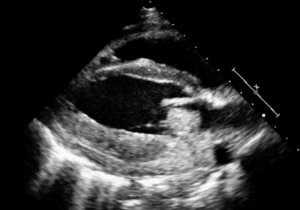

Når bakterierne først er i blodbanen, kan de adhærere til fibrin-clottet og i en ond cirkel af bakterievækst og fibrinaflejringer danne de vegetationer, man kan se for sig. Her er et eksempel på en vegetation på atriesiden af mitralklappen. Den store tumormasse, der nærmest blokerer indløbet til venstre ventrikel er en stor klump af bakterier og fibrin.

Ekkokardiografisk billede af endokarditis-vegetation på atriesiden af mitralklappen. Fra Rocust & Riveros, showmethepocus.com/pulmonary-embolism-endocarditis-masses, CC BY-NC 4.0.